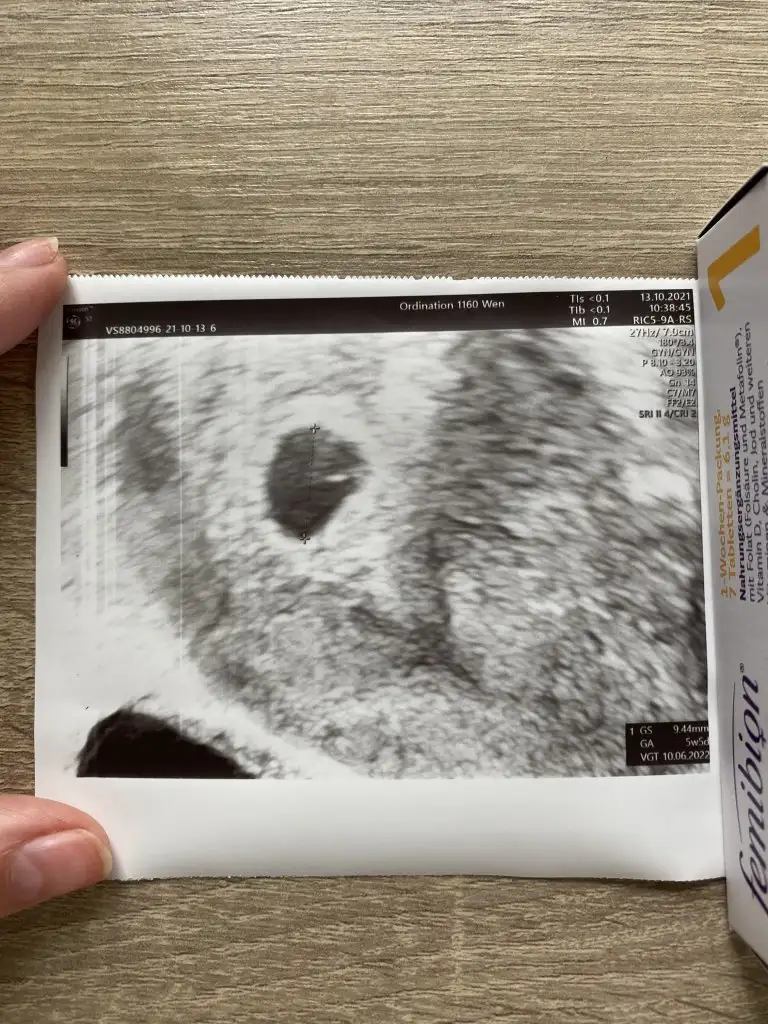

Canım ben yurtdışında yaşıyorum burda devlete gidiyorum çok tatlı bir doktorum var, bana fotoğrafda verdi kan aldı 2 tüp 3 hafta sonra gel dedi birde benim adetim 33-35 günde bir olduğu için daha çok küçük dedi.Ultrason fotoğrafını vermedi bana ama gösterdi keseyi. Bende şaşırdım ama birşey demedim keseyi gördüm rahatladığım için. Hatta sordum hocam normal mi diye erken daha normal kafana takma tekrar 1 hafta 10 gün sonra bakalım dedi. Bebeği görelim dedi.

Benim doktor direk alttan baktı ama ona güvendiğim için hiç bir şey demedimFotoğrafda bu